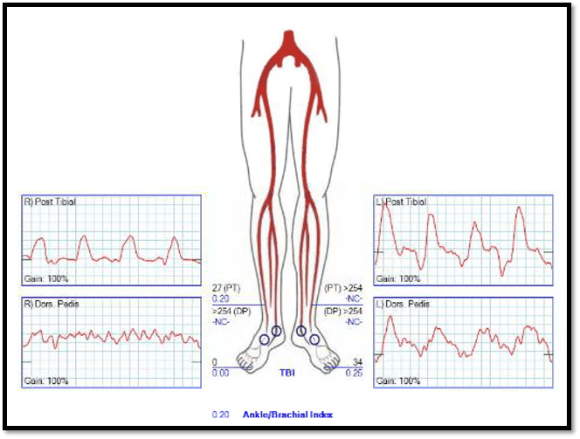

Preop ABI, TBI’s, toe waveforms, and pulse Dopplers are shown. are as shown.

preop TBI.pngpreop-abi

All point to likely limb loss. The TBI is 0 and the ABI is incompressible. Max planned for bypass. The saphenous vein was mapped and shown to be adequate.